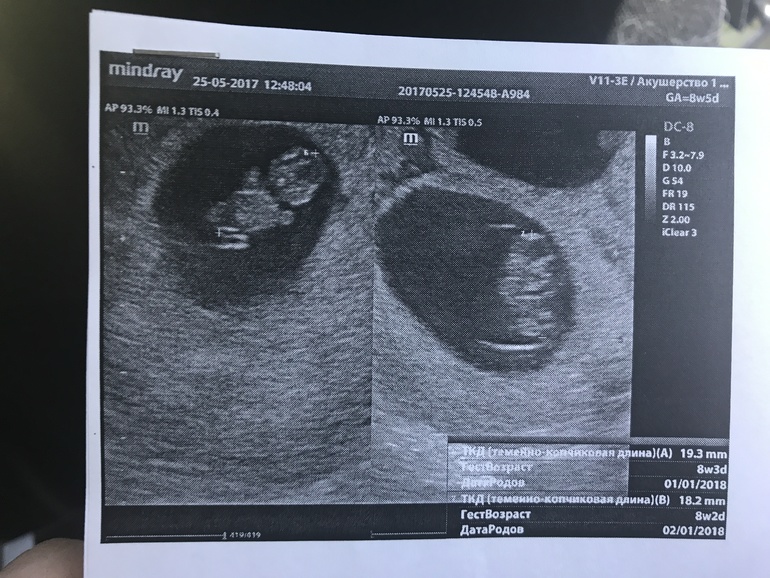

У нас будет двойня!!!

Но зато развиваемся по сроку, сердечко бьется и мы уже танцуем в животике))

Фото далее под кат.